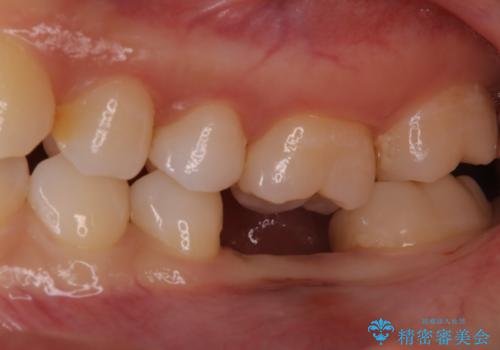

奥歯が残せないと言われた。『インプラント治療』

- 他院で抜歯と言われ、今後どうしたらいいのかを相談された患者様です。

抜歯を行った後は、Br、義歯、インプラント、何もしないという選択肢のメリットデメリットを説明させていただき患者様がインプラント治療を希望されたので今回治療させていただくことになりました。

歯のなかったところをインプラント治療を行うことによってまた噛める喜びを感じていただけて良かったと思っております。